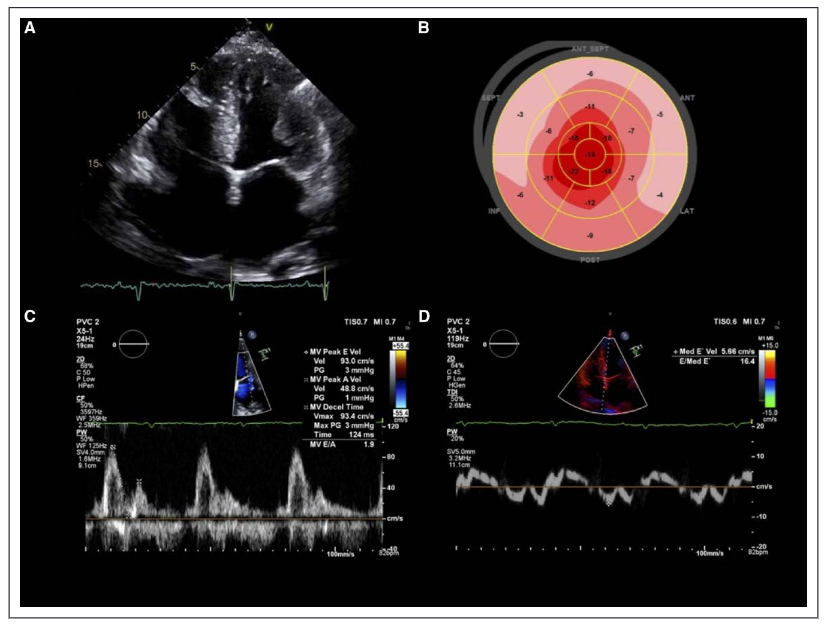

经胸超声心动图(tte)显示:左心室射血分数降低(lvef 30%),前壁,室间隔(5)

评价病毒性心肌炎(vmc)患儿治疗前后左心室心肌整体收缩功能的改变

超声心动图检测早期糖尿病心脏病变左室功能最佳部位的选择被引量:2

超声心动图显示左室壁适度增厚,舒张功能异常,左心室射血分数(lvef)为